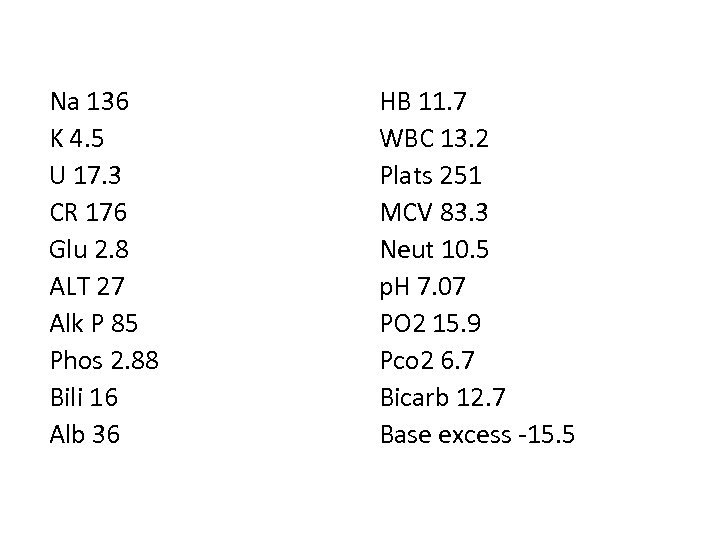

Na 136 K 4. 5 U 17. 3 CR 176 Glu 2. 8 ALT 27 Alk P 85 Phos 2. 88 Bili 16 Alb 36 HB 11. 7 WBC 13. 2 Plats 251 MCV 83. 3 Neut 10. 5 p. H 7. 07 PO 2 15. 9 Pco 2 6. 7 Bicarb 12. 7 Base excess -15. 5

Q. 10 Litres per minute of oxygen is administered an arterial blood gas is taken. Comment on the acid base and ventilation status of the patient and give reasons for the results, (3 marks )

Q 2. 10 Litres per minute of oxygen is administered an arterial blood gas is taken. Comment on the acid base and ventilation status of the patient and give reasons for the results, (4 marks ) • Mixed metabolic and respiratory acidosis (1 mark for acidosis, 1 mark for mixed)- probably sepsis and retained Co 2 (1/2 mark each) • Hypoxaemaia (Low oxygen) for the inspired concentration – likely secondary to V/Q mismatch